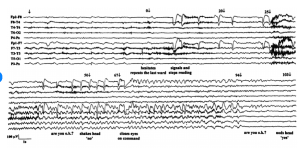

Take our EEG Test Questions!

Are you prepping for your EEG boards? 🧠📚

Engage with our community and enhance your knowledge in the neurodiagnostic field with our EEG Fun Facts. Each fact comes with a question and multiple choice answer to choose from to test your knowledge!